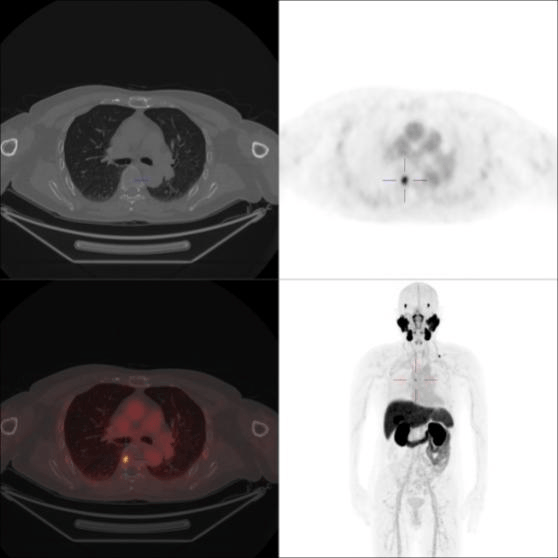

病例二

患者,男,72岁,前列腺癌术后7年余,连续3次tPSA>0.2ng/ml

左侧第2肋、T6椎体PSMA摄取增高灶,考虑转移瘤